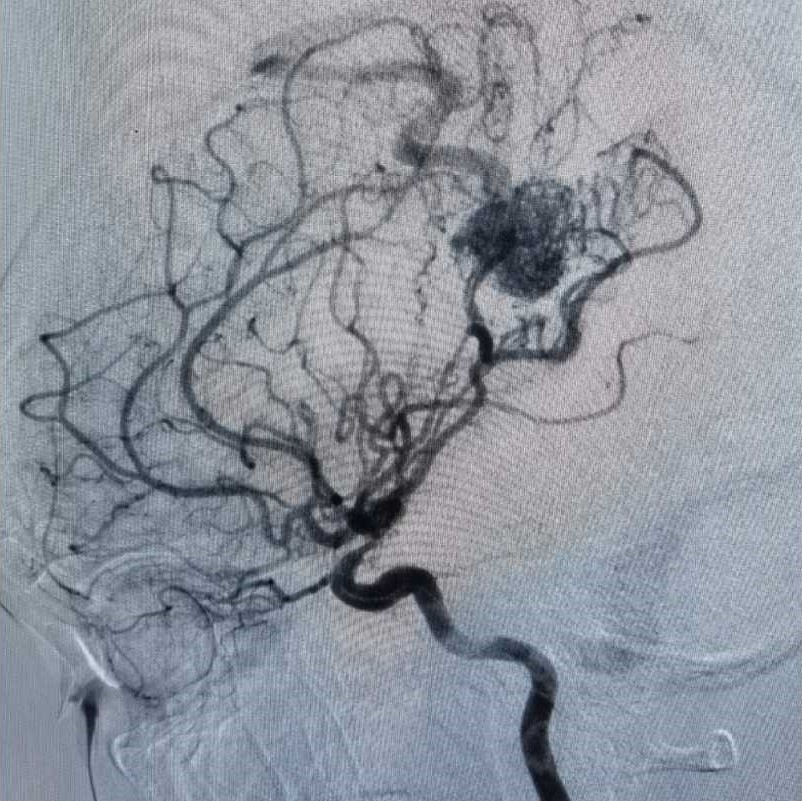

行DSA检查

显示畸形血管团为20*23mm,多支动脉参与供血,引流至上矢状窦。